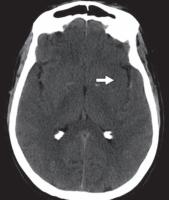

图 1C —大脑中动脉 (MCA) 梗塞。平扫 CT 图像显示右侧 MCA 高密度征(箭头)。

急性动脉梗塞会产生缺氧状态,伴随去极化、炎症、氧化或亚硝化应激以及细胞凋亡继发的 ATP 快速消耗。细胞毒性水肿在动脉闭塞后 30 分钟内出现,在梗塞后 24 至 72 小时达到峰值,并在再灌注后持续长达 24 小时。在 CT 上,灰白质界限的丧失发生在对应的血管分布位置。大脑中动脉梗死的早期迹象包括豆状核的遮蔽(图 1A )) 和岛带的丢失 (图 1B); 这些通常具有高灰白对比度的区域由小的脑动脉穿支供血。大的血管内血栓也可能表现为类似增强扫描的密度增高(高密度动脉征)(图 1C )。进行性水肿导致病灶整体体积增加,表现为脑沟、脑室和脑池的消失。